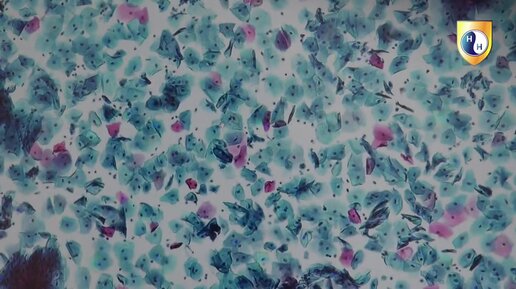

Дрожжеподобные грибы (Candida spp.) в микропрепаратах. Цитологический практикум. Видео 18.